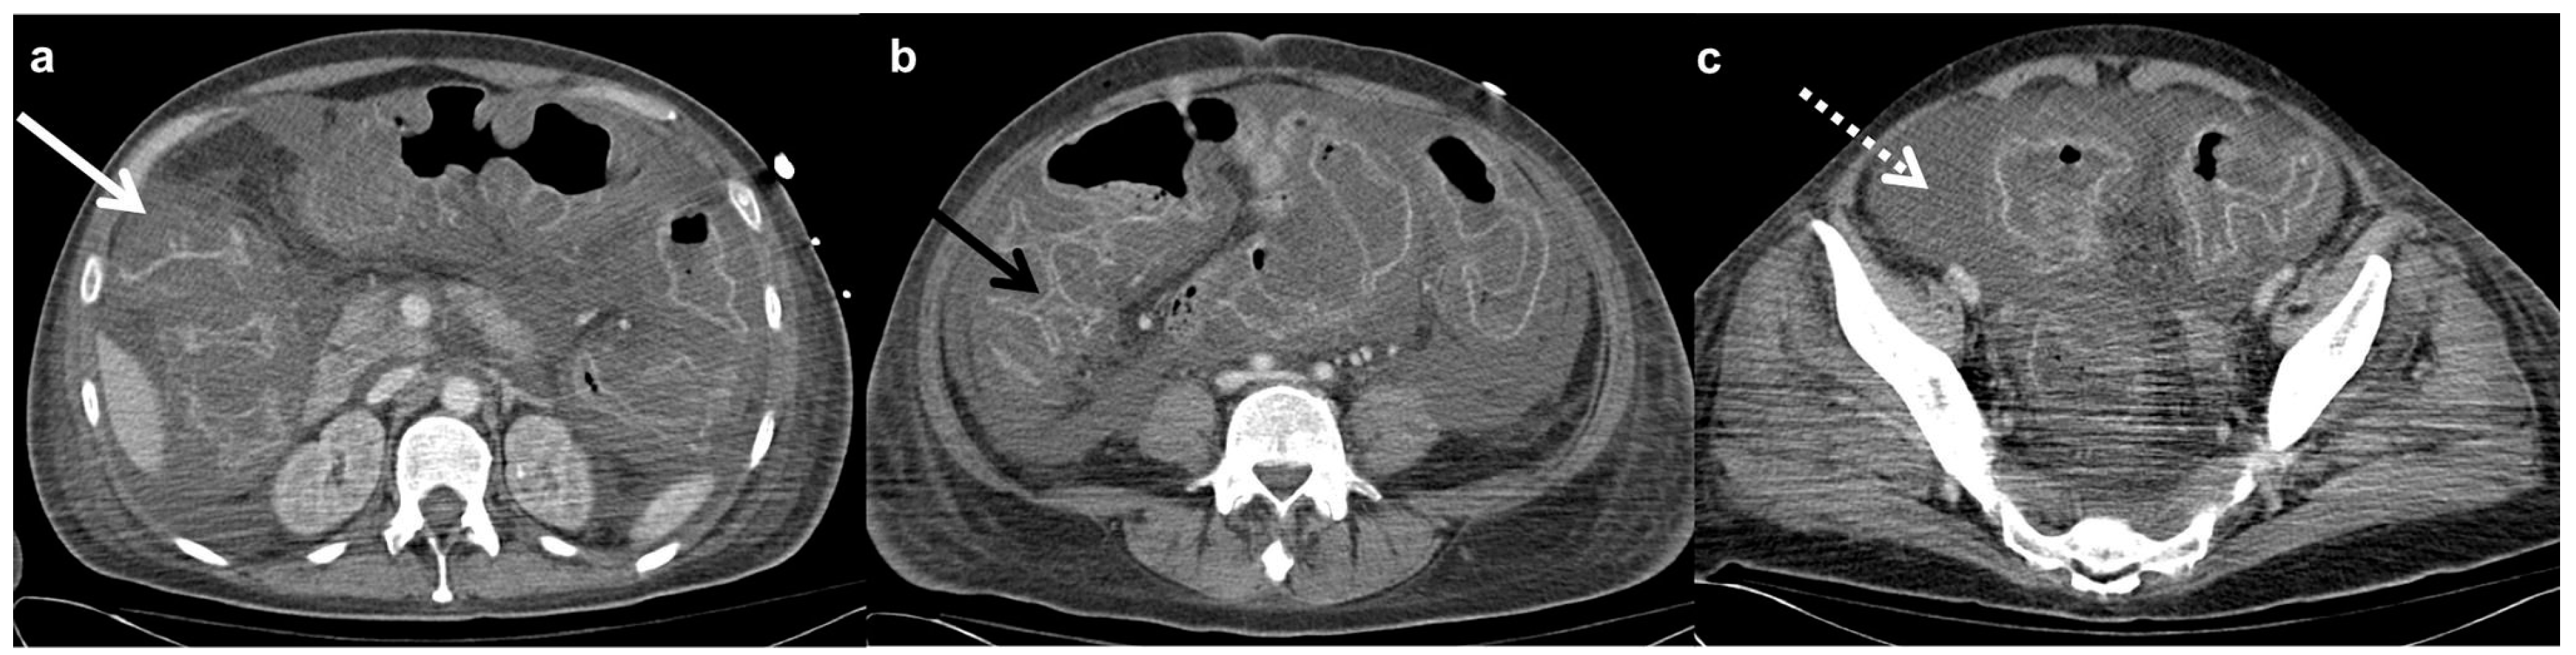

- Buckley, O.; Geoghegan, T.; O’Riordain, D.S.; Lyburn, I.D.; Torreggiani, W.C. Computed tomography in the imaging of colonic diverticulitis. Clin. Radiol. 2004, 59, 977–983. [Google Scholar] [CrossRef]

- Hulnick, D.H.; Megibow, A.J.; Balthazar, E.J.; Naidich, D.P.; Bosniak, M.A. Computed tomography in the evaluation of diverticulitis. Radiology 1984, 152, 491–495. [Google Scholar] [CrossRef]

- Destigter, K.K.; Keating, D.P. Imaging update: Acute colonic diverticulitis. Clin. Colon Rectal Surg. 2009, 22, 147–155. [Google Scholar] [CrossRef] [PubMed]

- Hachigian, M.P.; Honickman, S.; Eisenstat, T.E.; Rubin, R.J.; Salvati, E.P. Computed Tomography in the Initial Management of Acute Left-Sided Diverticulitis. Dis. Colon Rectum 1992, 35, 1123–1129. [Google Scholar] [CrossRef] [PubMed]

- Neff, C.C.; vanSonnenberg, E.; Casola, G.; Wittich, G.R.; Hoyt, D.B.; Halasz, N.A.; Martini, D.J. Diverticular abscesses: Percutaneous drainage. Radiology 1987, 163, 15–18. [Google Scholar] [CrossRef] [PubMed]

- Rao, P.M.; Rhea, J.T.; Novelline, R.A. Helical CT of appendicitis and diverticulitis. Radiol. Clin. N. Am. 1999, 37, 895–910. [Google Scholar] [CrossRef]